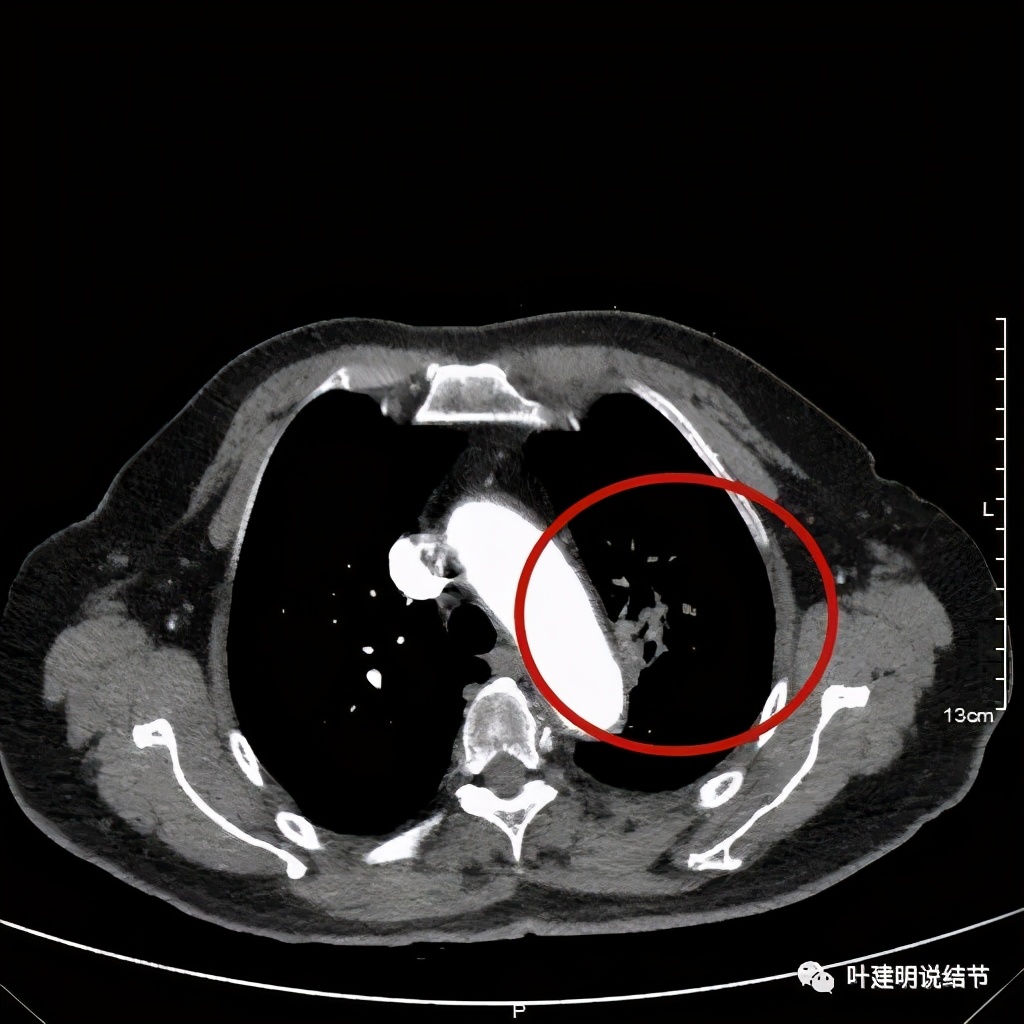

肺窗见原左上叶巨大占位已经明显缩小,甚至几乎不见了!而且上图示左上叶支气管清晰可见,内壁变光滑。纵隔窗增强又是如何的呢?

左上肺基本已经不见肿瘤,只在主动脉旁少许软组织影